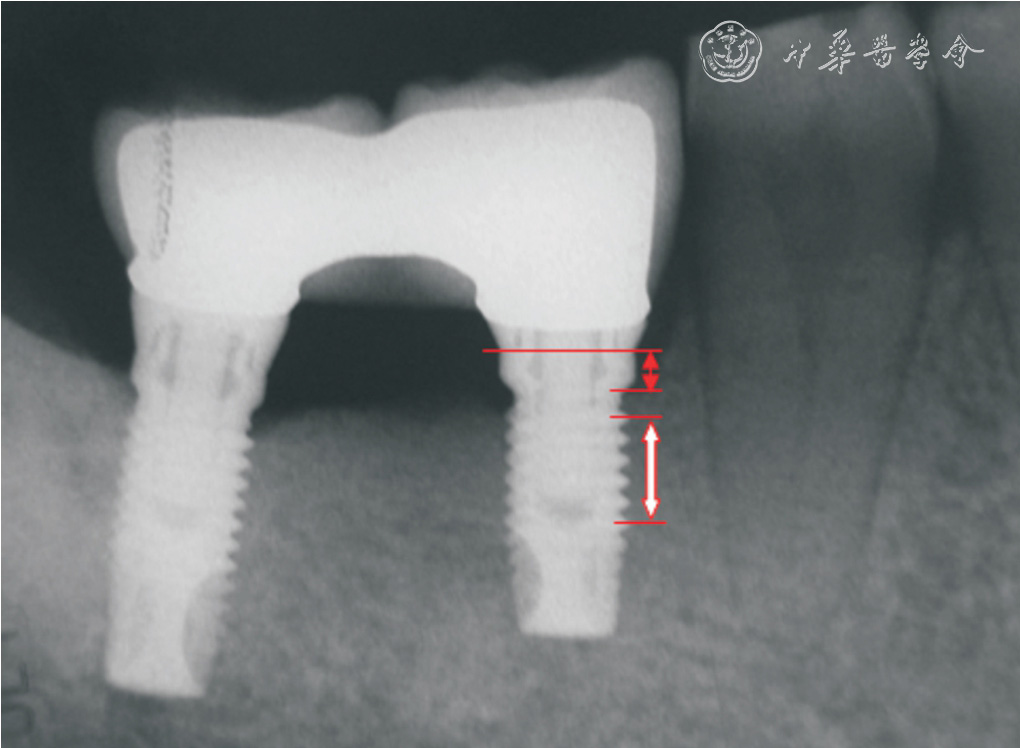

A total of 70 dental implants were placed in the posterior regions of 42 partially edentulous patients. 24 crowns were screw-retained, while 46 crowns were cementretained. Peri-implant marginal bone level, modified plaque index (mPLI), modified sulcus bleeding index (mSBI) and esthetic fulfillment were recorded at the 12 months recall after implant loading.

The mean peri-implant marginal bone lost in screw-retained group and cementretained group were 0.78 mm and 0.68 mm, respectively. The median values of mPLI and mSBI were both 1 in screw-retained group, and also 1 in cement-retained group. The median scores of esthetic fulfillment were both 1 in screw-retained and cement-retained group. The differences of marginal bone resorption, peri-implant soft tissue condition and patient satisfaction between two groups were statistically not significant (P >0.05).